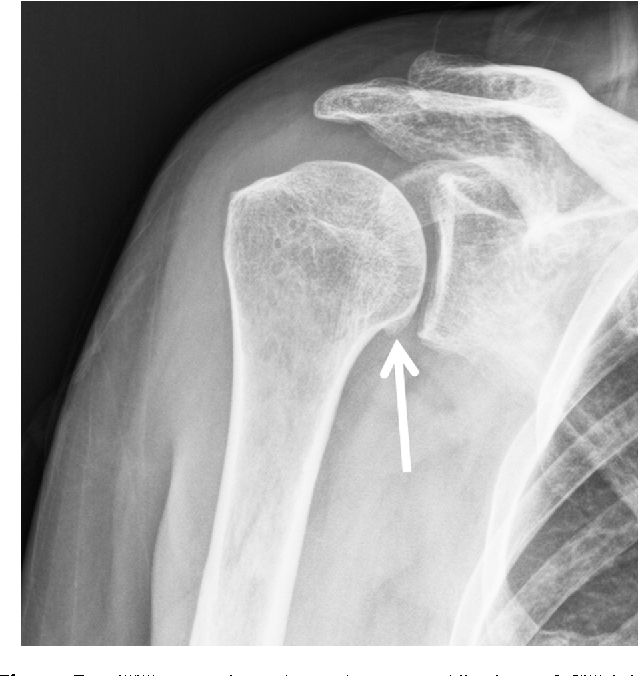

PA Oblique Shoulder (Grashey Method)

What position is demonstrated?